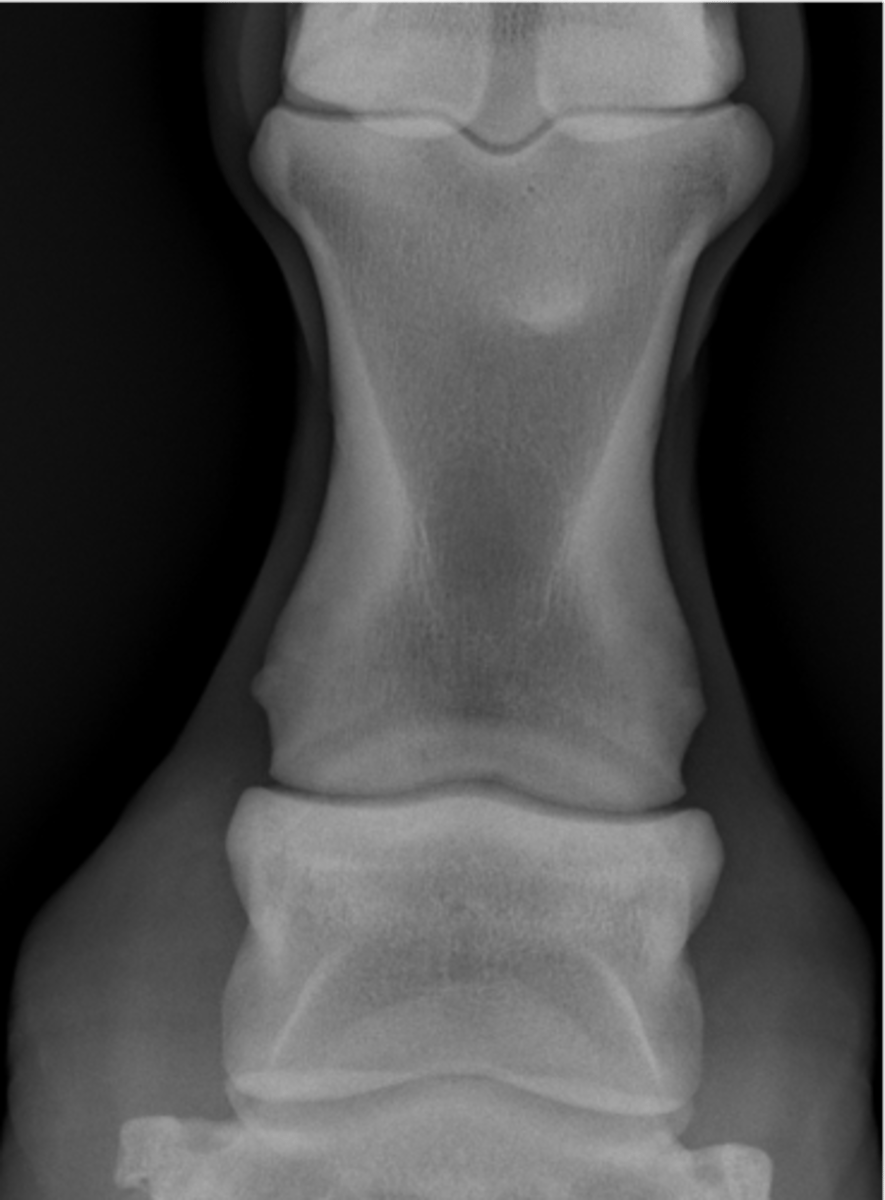

Coffin bone (P3)

Navicular bone

Coffin joint

Proximal interphalageal joint (pastern joint)

Short pastern (P2)

Upright pedal or high coronary

What view is this?